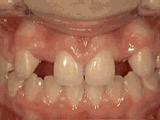

第一种:

前牙移位,因为有牙齿缺失,导致相邻牙齿开始没有秩序的前突,经过矫正后是变成这样的~